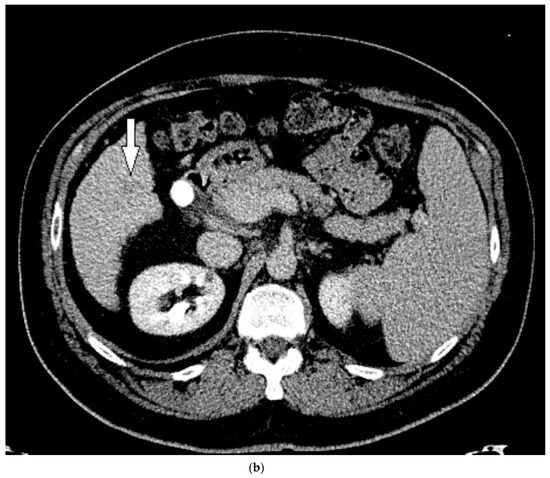

Figure 6.

Patient 3 CT images using liver windows to highlight the subtle enhancement and washout of the lesion seen on CEUS (white arrow): (a) late arterial phase axial contrast-enhanced CT; (b) 3 min delayed phase.

His liver function continued to decline during his stay, and within two weeks he received a deceased donor liver transplantation. HCC within the explanted liver was confirmed by histopathological examination, corresponding to the findings on CEUS. Upon review of the prior CT, for which a reduced contrast bolus (75 mL Omnipaque™ 350) was given due to his chronic renal disease, the tumor was subtle but faintly visible with the knowledge of its location based on the findings on CEUS (Figure 6).

On grayscale imaging, a 2.9 cm hypoechoic lesion at the dome of the right lobe on a background of heterogeneous liver parenchyma was identified (Figure 5). Due to his acute on chronic renal failure, CEUS was then performed, which showed subtle enhancement of the lesion, above background enhancement of the adjacent liver at the same depth. At or greater than 10 cm depth is most often the limit of penetration in standard CEUS software packages [13], but can be extended in the presence of ascites, as in our case. Subtle washout was identified on delayed imaging, and the lesion was deemed LI-RADS 5 (Figure 5).